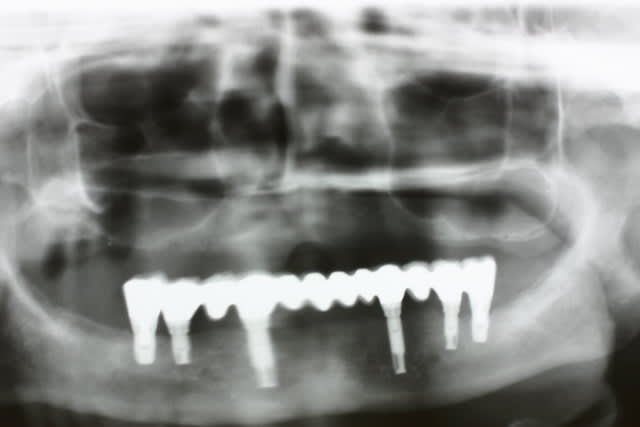

All on 4 ou all on 6 ça fait tjs pas bcp d implants

Ne me dites que je suis oiseau de mauvais augure ou ours mal léché mais j ai eu l occaz de voir de beaux all on 6 venant de la fac tout proche...si ces patients viennent me voir svt c est qu ils ont des problèmes dont le principal n est autre que la surcharge mécanique avec svt douleur et/ou perte d un implant distal car svt là ils posent du court et du gros diamètre, idéal pour avoir une belle lyse osseuse sur ce dernier

Que ce soit pour le all on 4 ou le all on 6 la sanction est la même : qd vous perdez un implant vous voyez tout le travail se casser la figure

Vous voyez que ds tout mes cas de basale, je pose bcp et stt je cherche systématiquement des ancrages POSTERIEURS

on parlait du maxillaire.

Certes oui mais c est le premier beau all on 6 sur lequel je suis retombé ds le PC